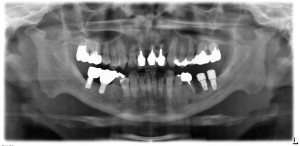

7番部位には、昨年の9月にGBRと同時埋入のスプライン8mmが入っています。

7番のインプラントは同時に2時オペも行っていますので、2か月後に上部構造製作のための印象採得へ移行できると思います。

7番部位には、粘膜下にインプラントが入っています。

術後のレントゲン写真です。